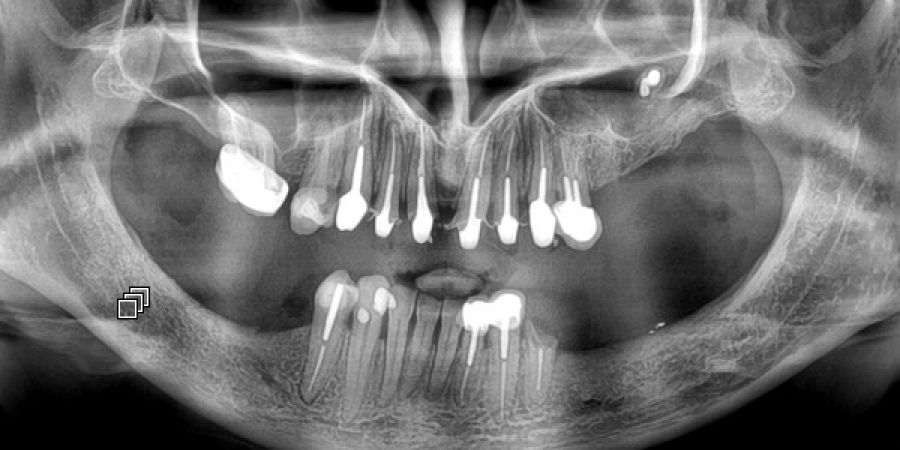

Fréquemment demandé et utilisé pour les soins dentaires, l'imagerie dentaire est aussi souvent utilisée pour la recherche de pathologies sinusiennes

Le panoramique dentaire est un appareil de radiographie qui effectue une rotation autour de votre tête afin de dérouler toute l'arcade dentaire sur un seul plan.